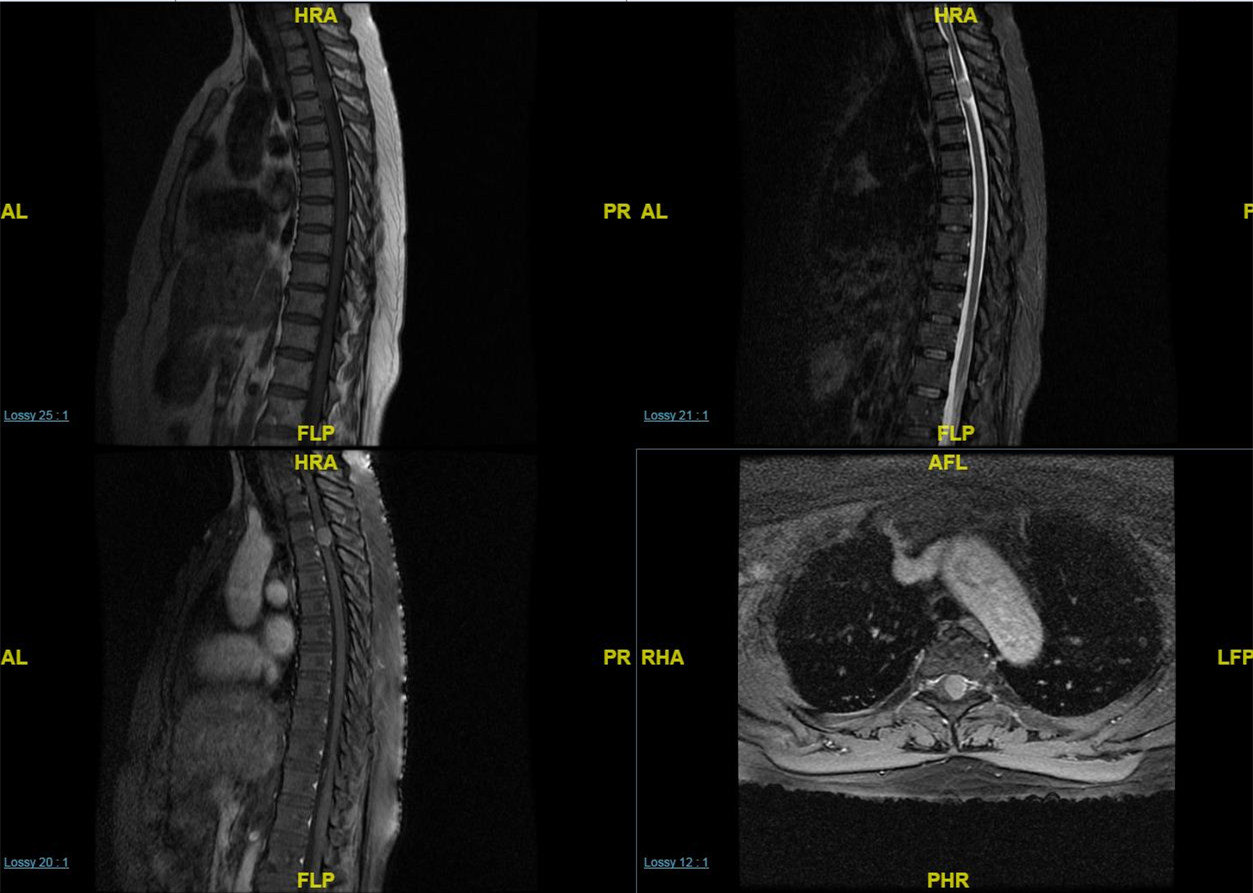

磁共振显示颈胸段椎管内占位病变,诊断"脊膜瘤"肿瘤切除干净,脊髓保护